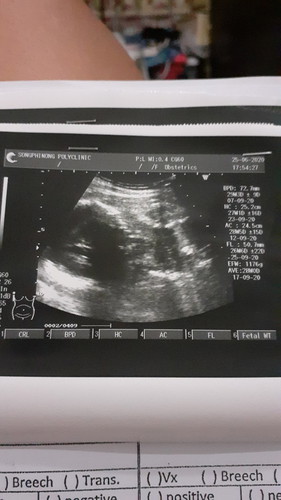

ยังไม่7เดือนลูกกลับหัวแล้ว

มีแม่ๆท่านไหนลูกกลับหัวตอน7เดือนบ้างค่ะ กังวลมากกลัวลูกออกก่อนกำหนด ปกติเด็กต้องกลับหัวตอนกี่เดือนค่ะ